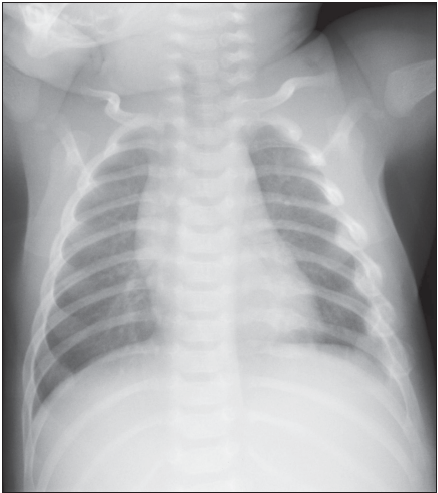

Infant With Purpura

04/29/2011

Randall Schlievert, MD; Gabriella Bene, MD

A 9-week-old Caucasian infant is brought to the primary care physician for evaluation of purpura and petechiae.